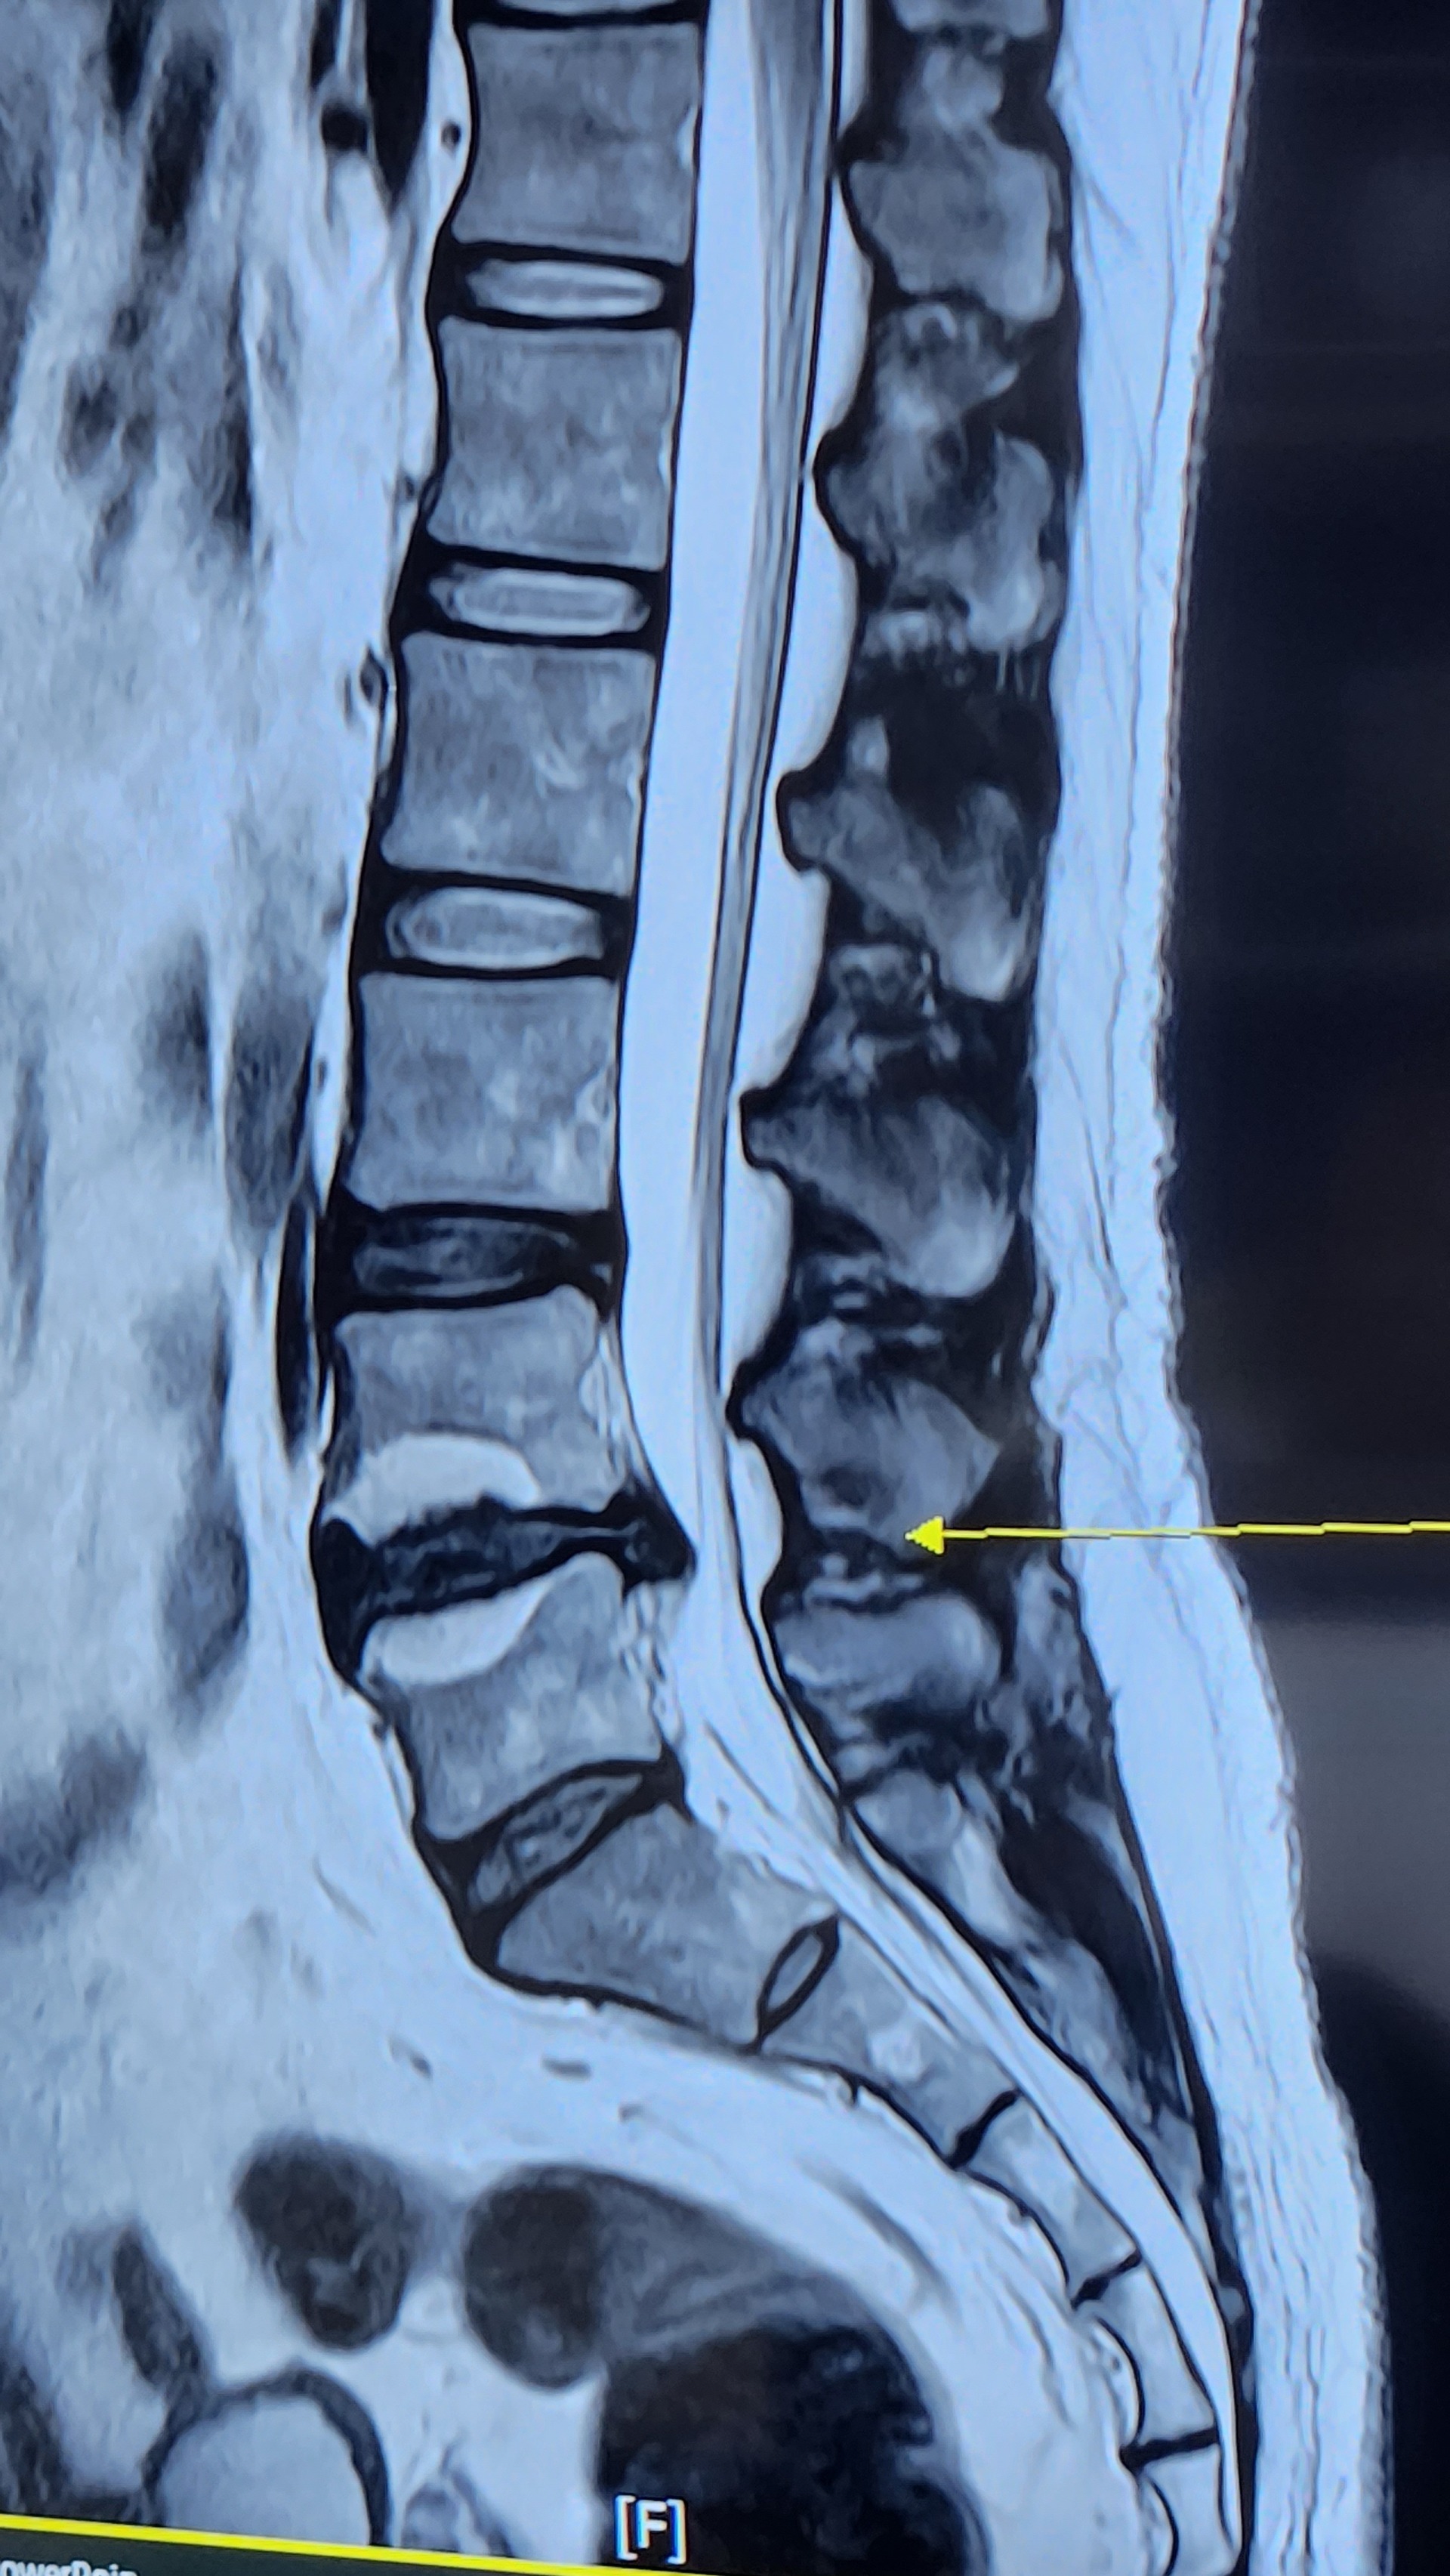

홈진료상담 및 문의 진료상담 및 문의 아들 허리 디스크 추간판탈출증 작성자 강혜정 (엄마) 작성일 2023-10-13 02:11 조회 247 아들88년생입니다. 허리 상태 이고요? 병원에서 수술해야된다고 하는데 치료해서 완쾌 될수있을까요? 가능하다면 방문하고 싶은데요? 좋아요 0 싫어요 0 인쇄 « 누구를 위한것인가 ccc » 목록보기 답글쓰기 글수정 글삭제 Powered by KBoard